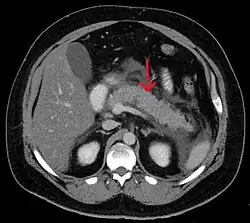

Acute exudative pancreatitis on CT scan -

Calcified pancreatic duct stones with some free intra-abdominal fluid